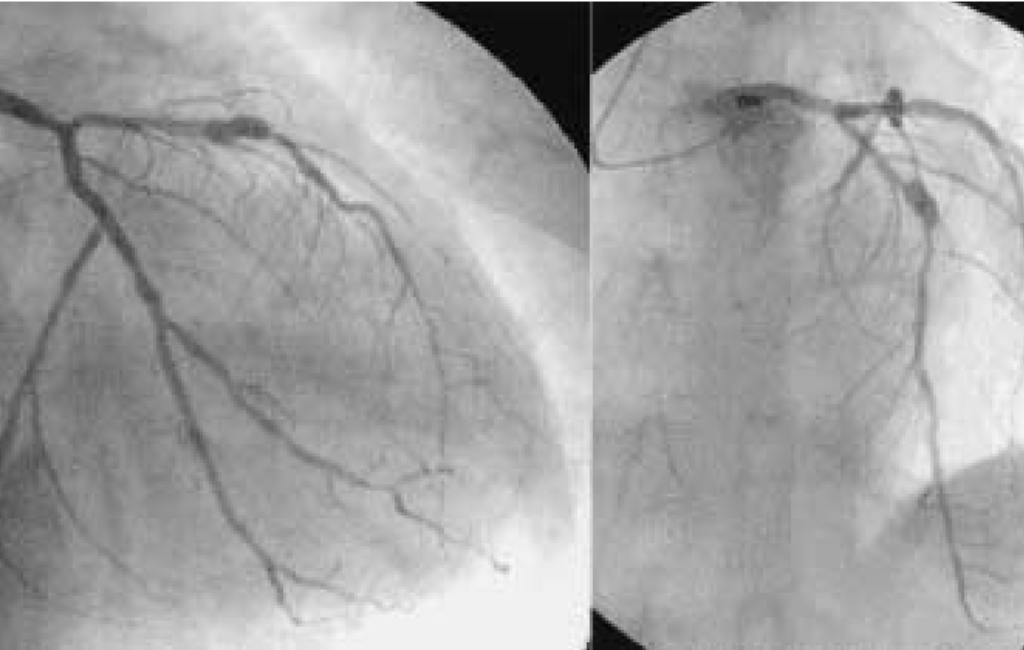

Before & After

Cardic Surgery Results